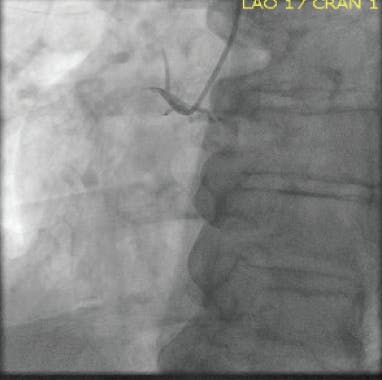

Angiography showed complete occlusion and heavy thrombus burden from the SVG to the diagonal branch (Figure 1). It was planned to intervene upon the lesion. The occlusion was determined to be acute based on a previous angiogram within the past month that showed a patent SVG to the diagonal branch. The lesion was wired using a 0.014-inch X 300-cm Sion® Blue wire (Asahi Intecc USA, Inc.) without any problems. Because the graft was totally occluded, it was decided not to advance a filter through the occlusion due to risk of distal embolization (Figure 2). Mechanical thrombectomy with CAT RX was used to aspirate the thrombus. After three runs of mechanical aspiration using a CAT RX and around 3 minutes of aspiration, TIMI 3 flow was restored (Figure 3). The patient was treated with heparin infusion overnight to reduce further thrombus burden and was brought back to the catheterization laboratory the next day for staged PCI with a DES (Figure 4).

Figure 1. Initial angiogram showing occlusion through the SVG.

Figure 2. Angiogram after wiring.

Figure 3. TIMI 3 flow through the SVG after using CAT RX.

Figure 4. Final angiogram after using CAT RX and staged PCI.